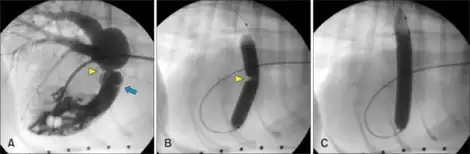

a)Pulmonary valve blue arrow and supravalvular pulmonic stenosis yellow arrowhead b)contrast solution across the stenotic lesion yellow arrowhead c) full inflation of balloon

The treatment of choice is percutaneous balloon valvuloplasty and is done when a resting peak gradient is seen to be >60mm Hg or a mean >40mm Hg is observed.